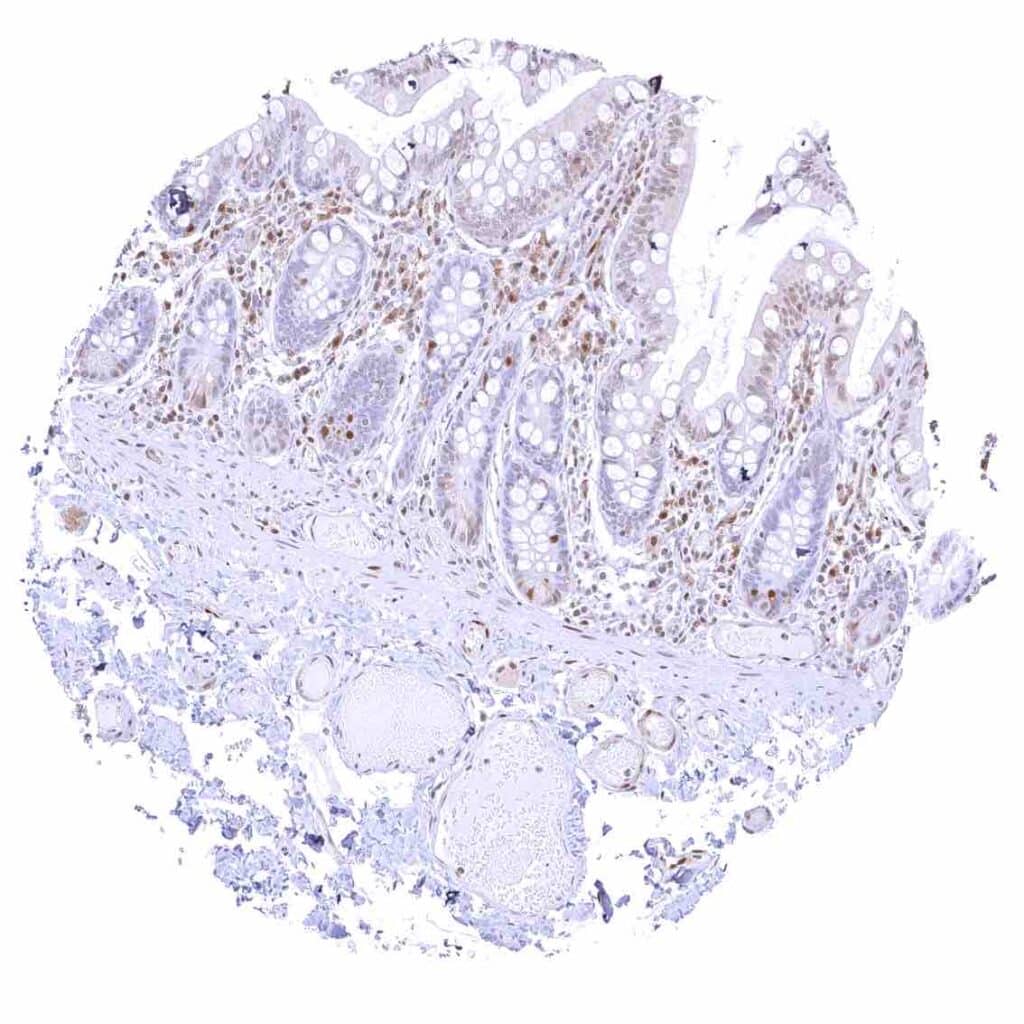

Rectum, mucosa